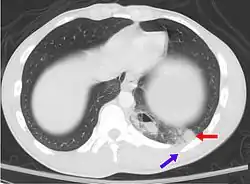

![]() | |

| A CT scan showing a pulmonary contusion (red arrow) accompanied by a rib fracture (purple arrow) | |